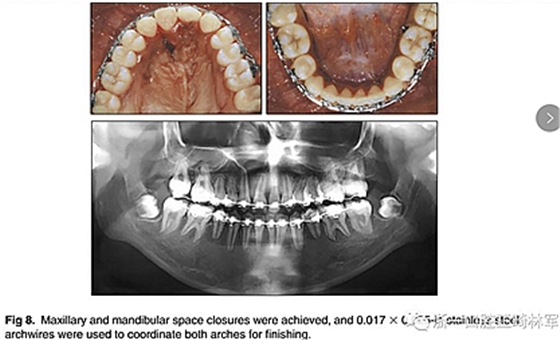

兩年半后,在上下牙弓上均實現(xiàn)了間隙關(guān)閉,并且使用0.017×0.025英寸的不銹鋼弓絲進(jìn)行咬合精細(xì)調(diào)整(圖8)。去除托槽后,上下頜采用舌側(cè)弓進(jìn)行保持(圖9)。